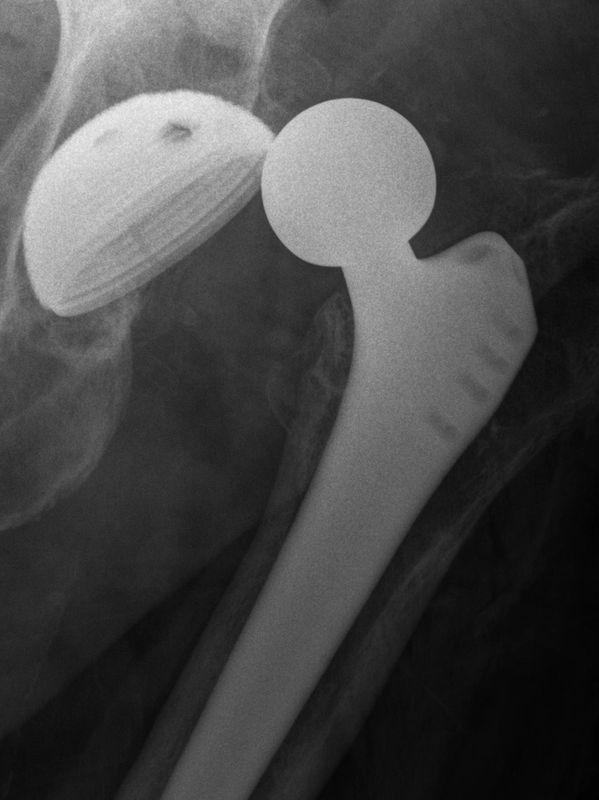

Subsequent spasm of the muscles longitudinally traversing the hip joint leaves the ball sitting behind the rim. The muscle spasm causes superior movement and further wedging of the ball. This can be seen in the X-ray above, and clinically as leg shortening and internal rotation.